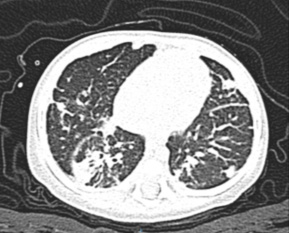

Se ha encontrado que las manifestaciones crónicas más frecuentes son anemia por infección crónica (65 %), linfadenopatía (52 %), hepatoesplenomegalia (25 %) y alteraciones gastrointestinales (25 %). A nivel pulmonar son más frecuentes bronquiectasias, bronquiolitis obliterativa y fibrosis crónica (figura 2). Por otra parte, las manifestaciones cutáneas incluyen fotosensibilidad, lesiones granulomatosas y vasculitis.6,23

Figura 2 Complicaciones pulmonares crónicas en enfermedad granulomatosa crónica ligada al cromosoma X